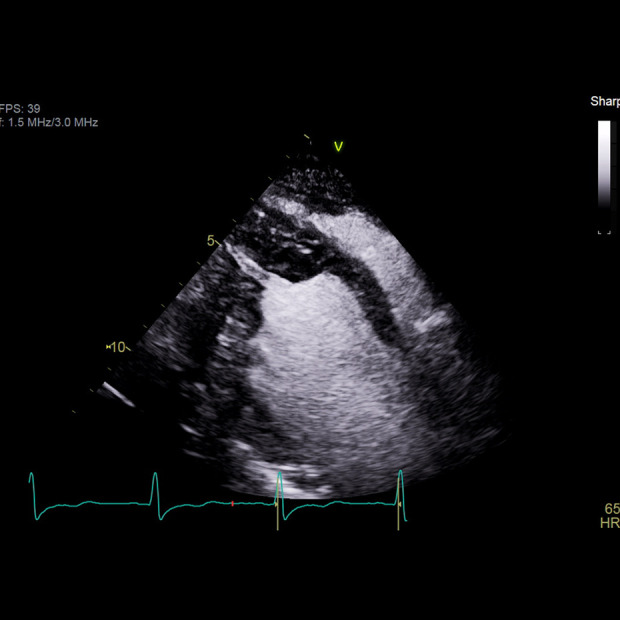

背景:顶端肥厚性心肌病(ApHCM)是一种罕见的变异,很少与肌瘤突变相关,缺乏特定的诊断和风险分层指南。病例报告:我们报告一例41岁男性,有复杂的病史,包括1型糖尿病和酒精使用障碍,在饮酒后出现恶心和呕吐。初步评估显示明显的电解质失衡和非持续性室性心动过速(NSVT)。超声心动图显示严重的根尖肥大,符合ApHCM。患者出现多形性室性心动过速,并发展为心室颤动(VF),需要心肺复苏(CPR)和重症监护。植入式心脏转复除颤器(ICD)成功植入二级预防。结论:本报告重点介绍了ApHCM的临床表现和治疗,强调了致心律失常风险的挑战和难治性室性心律失常的可能性。手术干预,如根尖肌切除术,可以改善功能能力。该病例强调了对ApHCM患者量身定制管理策略的迫切需要,特别是那些有物质使用障碍的患者,标准治疗可能是禁忌症。

BACKGROUND Apical hypertrophic cardiomyopathy (ApHCM) is a rare variant that is less frequently associated with sarcomere mutations and lacks specific diagnosis and risk stratification guidelines. CASE REPORT We present the case of a 41-year-old man with a complex medical history, including type I diabetes mellitus and alcohol use disorder, who presented with nausea and vomiting following alcohol consumption. Initial evaluations revealed significant electrolyte imbalances and non-sustained ventricular tachycardia (NSVT). Echocardiography indicated severe apical hypertrophy consistent with ApHCM. The patient developed polymorphic ventricular tachycardia, which progressed to ventricular fibrillation (VF), necessitating cardiopulmonary resuscitation (CPR) and intensive care. An implantable cardioverter-defibrillator (ICD) was successfully implanted for secondary prevention. CONCLUSIONS This report focuses on the clinical presentation and management of ApHCM, emphasizing the challenges of arrhythmogenic risks and the potential for refractory ventricular arrhythmias. Surgical interventions, such as apical myectomy, can improve functional capacity. This case underscores the critical need for tailored management strategies in patients with ApHCM, particularly in those with substance use disorders, where standard therapies may be contraindicated.